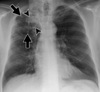

Considerando um paciente de 6 meses de idade, quais achados nessa radiografia indicam uma possível Tuberculose Pulmonar primária?

Linfonodomegalia mediastinal (seta) e consolidação nos lobos médio e inferior direito (cabeça de seta)